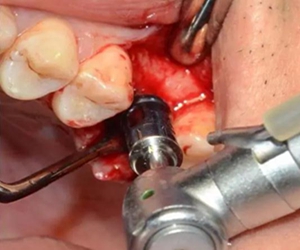

用配套工具進(jìn)行水壓式?jīng)_頂,提升竇膜。手感力反饋和回吸正常。在沖壓水量上要控制,緩慢反復(fù)多次抽吸,確保竇粘膜提升均勻。